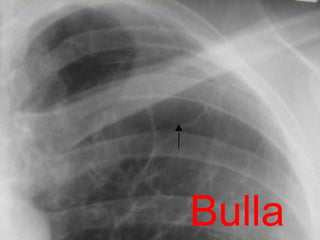

Bulla